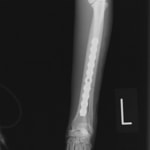

症例3:キルシュナーワイヤーのピンニングによる整復

ペルシャ猫 11ヶ月齢 雄

他院にて左大腿骨遠位の成長板骨折(salter-harrisⅠ型)が認められており、治療相談を目的として来院。当院にて、キルシュナーワイヤーを用いたピンニングにより骨折部位の整復を行いました。術後の経過は良好で、現在も経過観察中です。

術前レントゲン

術後レントゲン